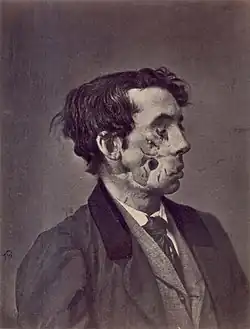

| 1865 illustration of a private injured in the American Civil War by a shell two years previously | |